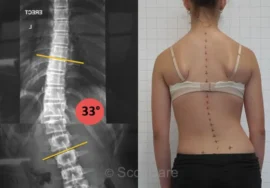

يعاني العديد من المراهقات من اعوجاج العمود الفقري، أو ما يُعرف طبيًا بـ الجنف المراهقي مجهول السبب (Adolescent Idiopathic Scoliosis – AIS)، وهو انحناء جانبي غير طبيعي للعمود الفقري يظهر غالبًا خلال مرحلة النمو السريع. من أكثر الأسئلة التي تشغل بال الأهل: هل هناك علاقة بين توقيت البلوغ وشدة الانحناء؟ وهل يمكن التدخل مبكرًا لمنع تفاقمه؟

ما العلاقة بين سن الحيض الأول وزاوية كوب (Cobb Angle)، وهي المعيار الطبي لتحديد درجة الانحناء؟

الفتيات اللاتي تأخرن في البلوغ كان لديهن زاوية كوب أكبر، ما يعني أن الانحناء يكون أكثر حدة.

هناك علاقة واضحة بين توقيت البلوغ وشدة اعوجاج العمود الفقري لدى البنات.